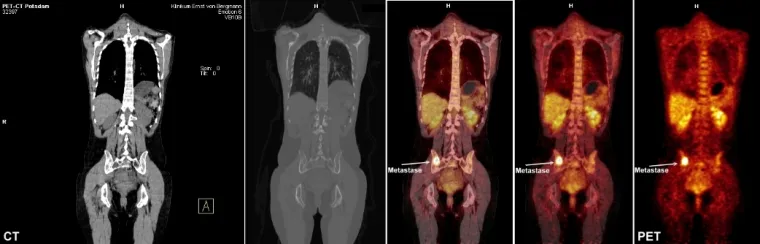

Die Innovation des PET-CT: durch die Fusion von CT- und PET-Bildern lassen sich Tumorerkrankungen früher erkennen; auch das Stadium einer Krebserkrankung kann exakter bestimmt werden.

Mittels der so genannten Bildfusion, also der digitalen Überlagerung von PET und CT-Informationen, können vom Arzt die Ergebnisse beider Untersuchungsverfahren ausgewertet werden. Die Auffälligkeiten im (Glucose )Stoffwechsel – sichtbar durch die PET – können durch die CT-Bilder nun eindeutig den entsprechenden Organen zugeordnet werden. Diese genaue Diagnostik ermöglicht es den behandelnden Ärzten, das komplette Behandlungsspektrum für den Einzelnen perfekt ausnutzen zu können und individuelle Therapiepläne zusammenzustellen.

Zurzeit beziehen sich die Anforderungen an PET-CT fast ausschließlich auf das Gebiet der Tumordiagnostik. Durch die Kombination aus funktioneller und morphologischer Diagnostik mittels PET-CT ist nicht nur ein frühzeitiges Erkennen von Tumorgewebe möglich, sondern auch die therapierelevante Festlegung des Tumorstadiums.

Mit PET-CT können Tumoren häufig schon nachgewiesen werden, wenn sie noch keine Tochtergeschwülste (Metastasen) in Lymphknoten oder anderen Körperregionen gebildet haben.

Aber auch wenn Metastasen vorliegen, wird vor einer eventuellen Operation, Bestrahlung oder Chemotherapie eine genaue Lokalisation des Tumor- und Metastasengewebes ermöglicht. Nach erfolgter Therapie kann mit dieser Methode der Therapieerfolg nachgewiesen werden.